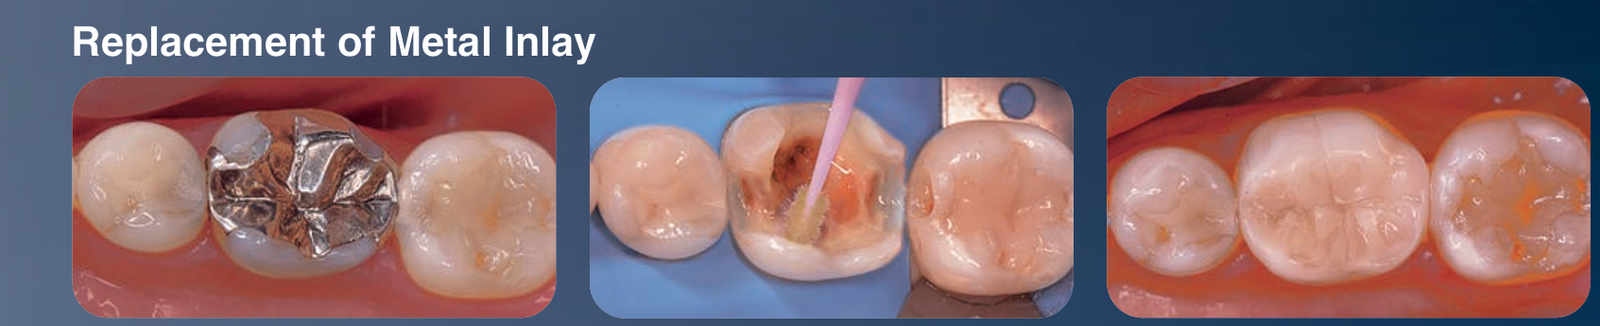

Replacement of Metal Inlay with Beautifil Injectable X

- Presents a clinical case demonstrating the replacement of a metal inlay with Beautifil Injectable X.

- Illustrates the application of BeautiBond Xtreme in the process, showcasing its bonding capability.

- Illustrates the application of Beautifil Injectable X in the last step.